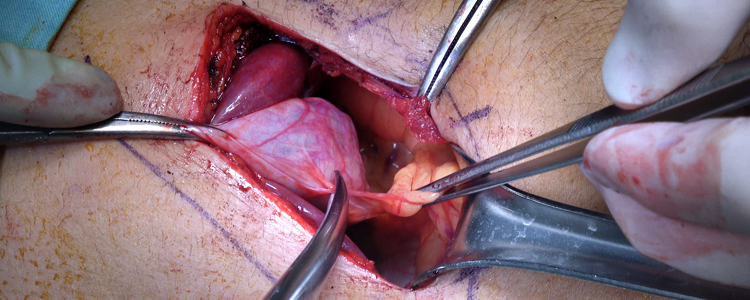

Complicated SSTIs can also be labeled as non-necrotizing or necrotizing infections. Necrotizing infections maximum typically contain the muscular fascial layers but may additionally contain the dermal, subcutaneous, and muscle layers and warrant activated, competitive surgical debridement.

Necrotizing SSTIs (cellulitis, fasciitis, myositis, Fournier’s gangrene) require surgical intervention which includes drainage and debridement of necrotic tissue further to antibiotic remedy.